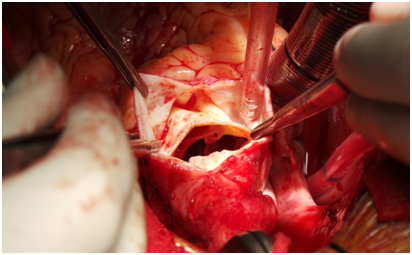

Bentals( Aortic Root Replacement ) Surgery

Surgery of Replacing The Ascending Aorta using Artificial Valved Conduit

Artificial Graft And anastomosing the Coronary Buttons

Replacement of Diseased Aorta with a Artificial Graft